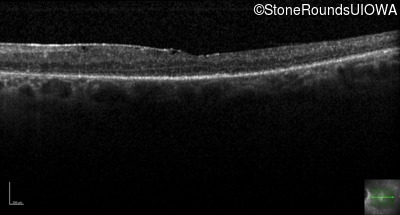

Optical Coherence Tomography - Right - 20/125

Exemplar / OCT Stack

OCT Stack